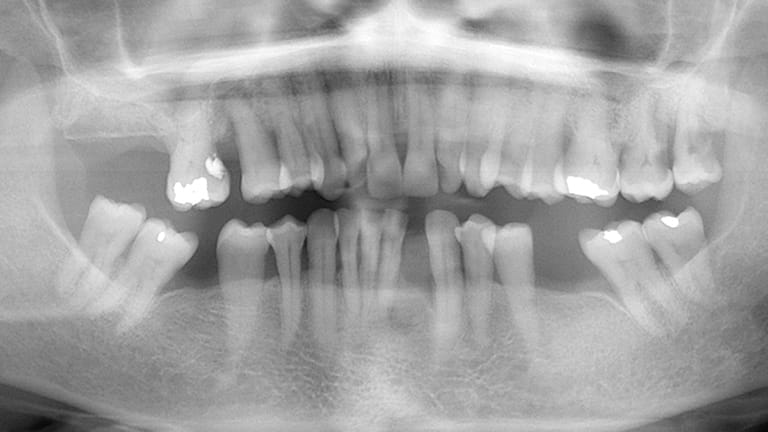

Dental implants are a titanium "root" which can be placed into the jawbone. Once integrated with your bone, the implant can be used to support a crown, a bridge, or secure a complete denture. Dental implants may be used to eliminate partial plates and dentures. The success rates for dental implants are extremely high which is due in part to the fact that root-form implants are made of a biocompatible material, titanium.

Below is a few examples of what DENTAL IMPLANTS can do for you and your smile!